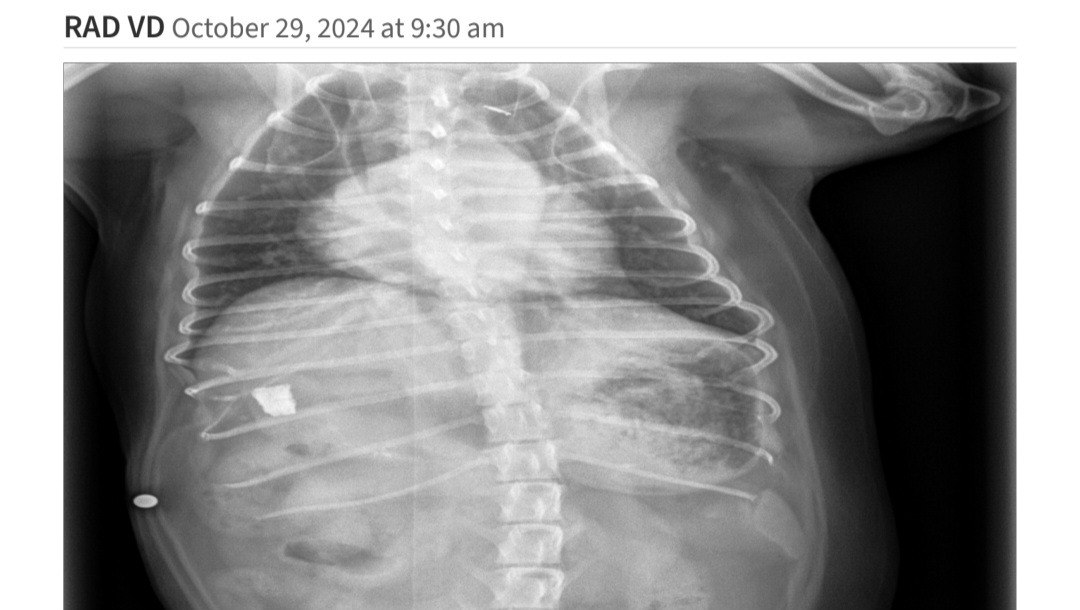

Little Freydis Potatis has been vomiting sporadically for a couple weeks, and we took her to the vet a few times to try and figure out why. When we took x rays on her most recent visit, we discovered that she swallowed an unknown object, and it's currently just vibing out in her stomach.